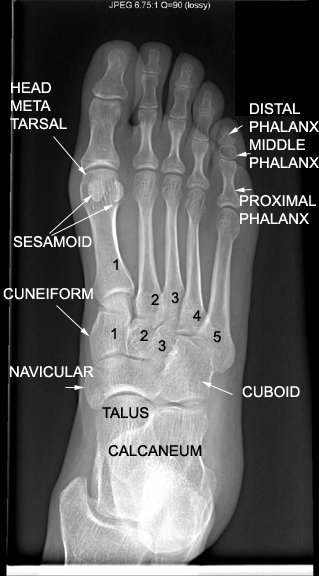

Identify the bones seen. Click the image for labeling.